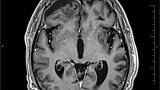

Иллюстрация №3: Рис. 3. Постоперационные изменения в правой лобной доле, отсутствие признаков опухолевого поражения в левой височной доле.

Вторым этапом комплексного лечения лимфомы головного мозга, с 20.11.18г. по 26.12.18г. в ФГАУ «Лечебно-реабилитационный центр» был выполнен курс 3D конформной дистанционной лучевой терапии на весь объем головного мозга в РОД -2 Гр до СОД 36 Гр с последующим увеличением на зону остаточной опухоли в РОД -2Гр до СОД 46 Гр. По данным контрольной МРТ головного мозга от 31.01.2019г: постоперационные кистозно-глиозные изменения в правой лобной доле, уменьшение постоперационной гидромы справа. МР-признаки опухолевого поражения в левой височной доле не обнаружены (рис 3). Таким образом, удалось добиться стабилизации опухолевого процесса в головном мозге. Реабилитационный период продлился три месяца.